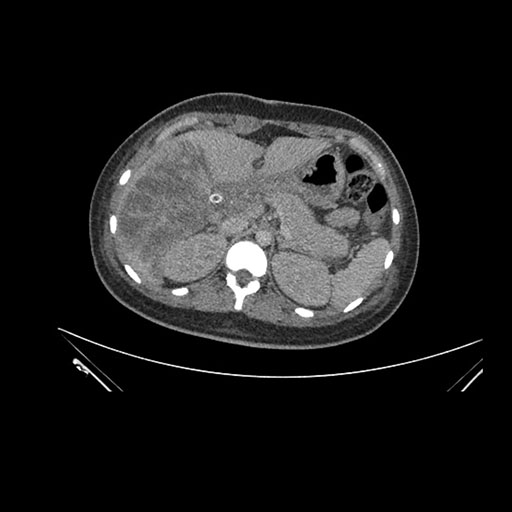

Axial Arterial

Axial Venous